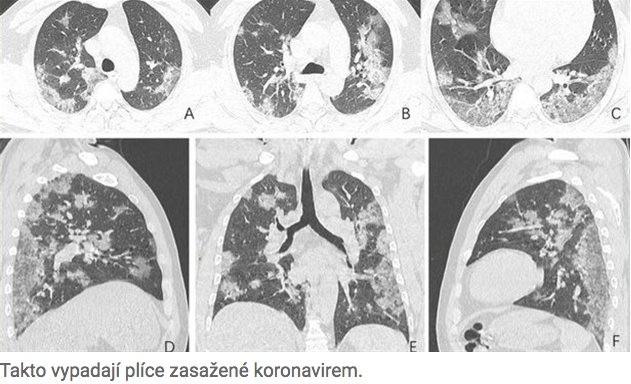

Even a layperson can tell that something is wrong with these lungs. Experts from the Radiological Society of North America (RSNA) published X-ray images of patients who died from the coronavirus, and it’s not a pleasant sight. The lungs are full of white spots — the so-called ground-glass density, where air spaces become partially filled. This then causes severe breathing difficulties.

American scientists have mapped exactly how the more severe form of the coronavirus affects the lungs. They even published X-rays of patients who died from the coronavirus.

You don’t have to be a doctor to recognize that something is wrong with the lungs in the picture. They are covered with a large number of white spots of various sizes. These are by no means a natural occurrence.

This is the so-called ground-glass density.

Air spaces in the lungs become filled, which then causes infected patients to suffer acute respiratory distress, lung pain, and other problems.

The X-ray shown above belongs to a 54-year-old Chinese patient who contracted the coronavirus at a market. Despite intensive treatment, he died after a week.